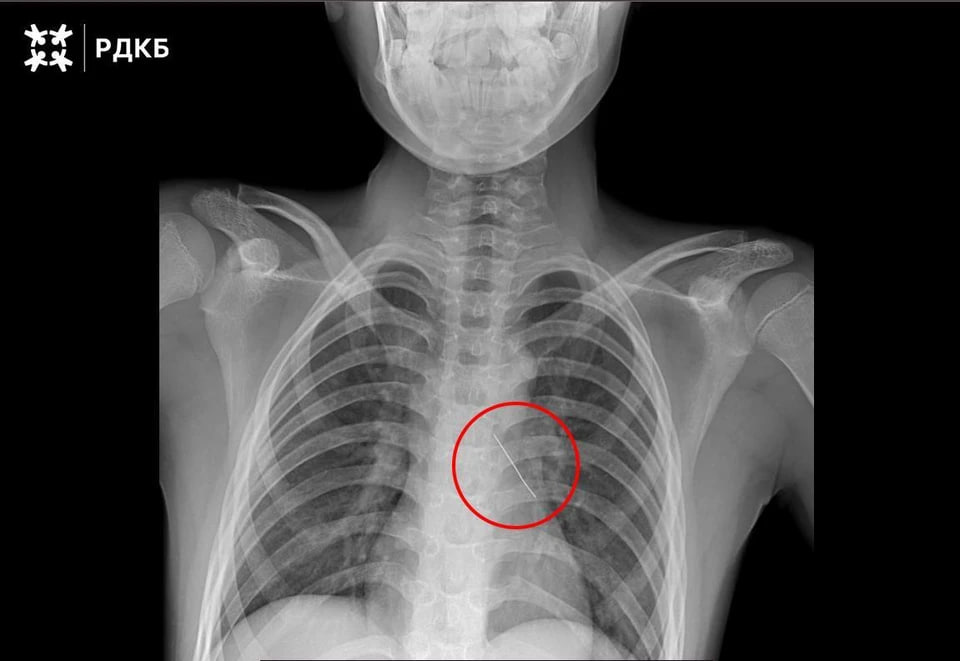

Изогнутая французская булавка пронзила бронх, что могло привести к серьезным нарушениям дыхания и даже коллапсу легкого. 11-летнего пациента доставили в столицу бортом санавиации. Мальчик мог только шептать и испытывал сильные боли.

Хирурги извлекли инородное тело с помощью оптических щипцов. Кровотечение купировалось самостоятельно. Через три дня после успешной операции ребёнка выписали.

Фото: тг-канал Российской детской клинической больницы